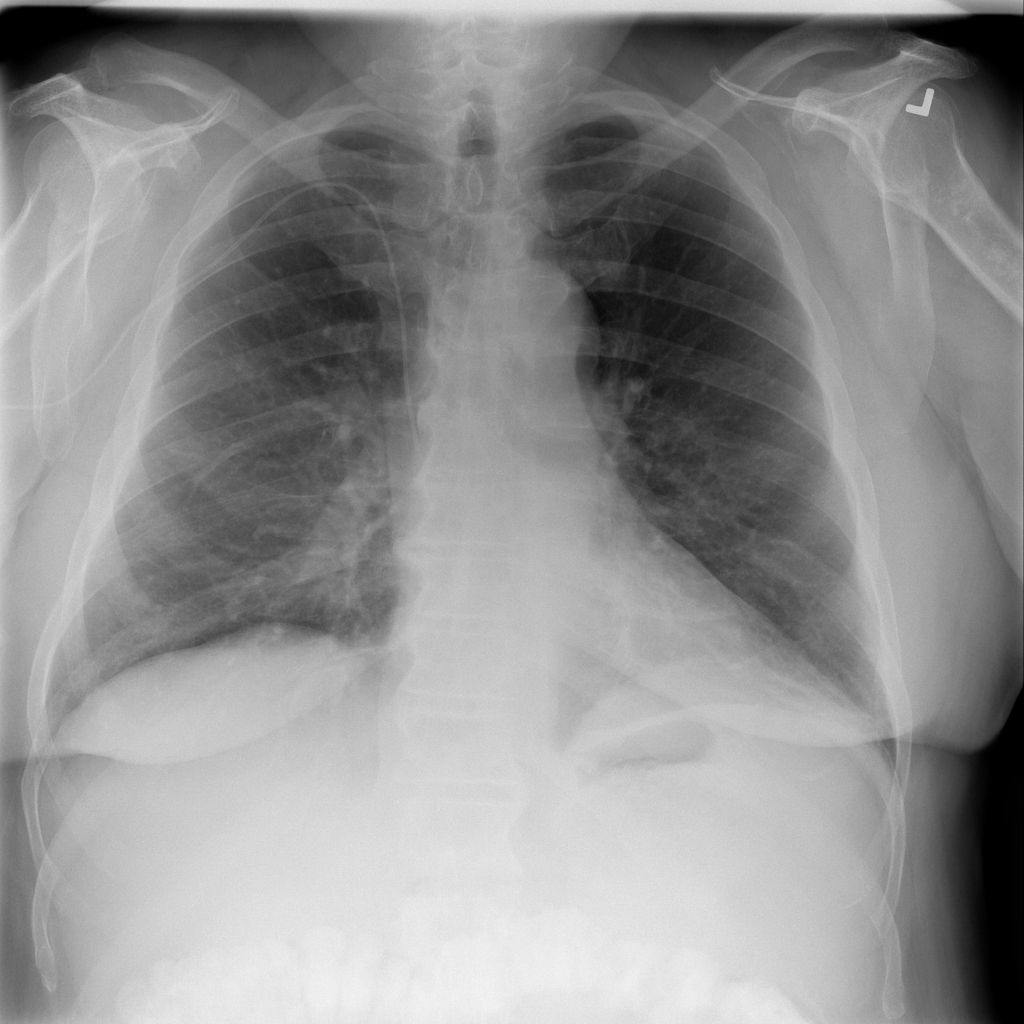

Pleural Effusion

Pleural effusion means extra fluid has collected around the lung in the pleural space. It can happen with heart problems, infection, inflammation, or other underlying conditions.